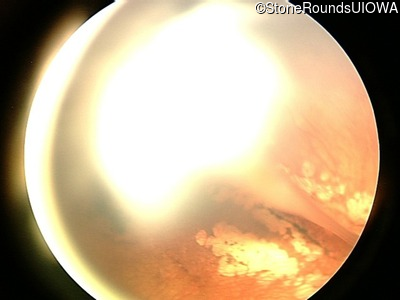

Fundus Photography - Left - 20/200

Exemplar